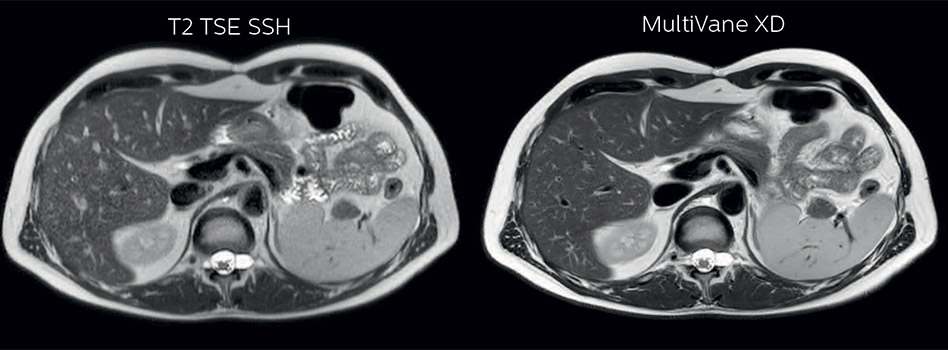

In this example the image quality of the MultiVane XD images is evidently better than in the images without MultiVane XD. Ingenia 1.5T with dS Torso coil solution.